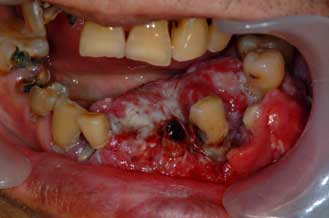

については繰り返し切除手術(反復掻爬術)を行う必要があります。腫瘍が大きくなり、広範囲

にあごの骨が吸収している場合はあごの骨を部分的に離断し、切除することが必要な場合があり

ます。あごの骨を部分的に離断、切除した場合にはチタン製プレートによる固定や骨移植を行い

再建する必要があります。

| エナメル上皮腫切除後(下顎骨) | チタン製プレートによる再建 | |